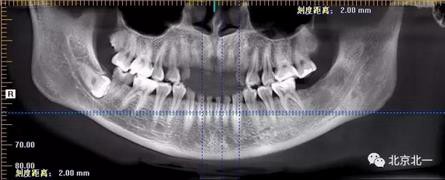

圖二:自帶的CBCT顯示下牙槽神經(jīng)管貼著智齒走形。

圖三:截面圖顯示神經(jīng)管位置。